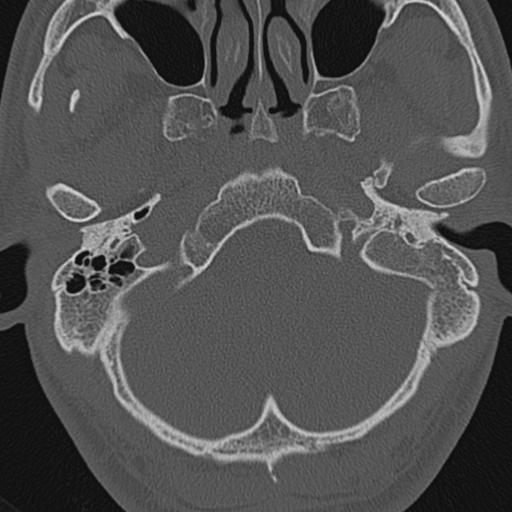

以下是引用zxl51642在2009-8-25 13:37:00的发言:[br]1、左侧慢性硬化型中耳乳突炎(中耳鼓室腔及听小骨受累),并胆脂瘤形成;2、左侧外耳道软组织密度影填塞,考虑炎性肉芽肿,建议结合临床;3、右侧颈静脉窝较左侧明显扩大,不排除颈静脉球瘤,建议mr进一步检查。

以下是引用随光逐影在2009-8-25 19:05:00的发言:[br]1)左侧慢性中耳乳突炎(肉芽肿或胆脂瘤形成),左侧外耳道炎性肉芽肿。2)右侧颈静脉球高位。